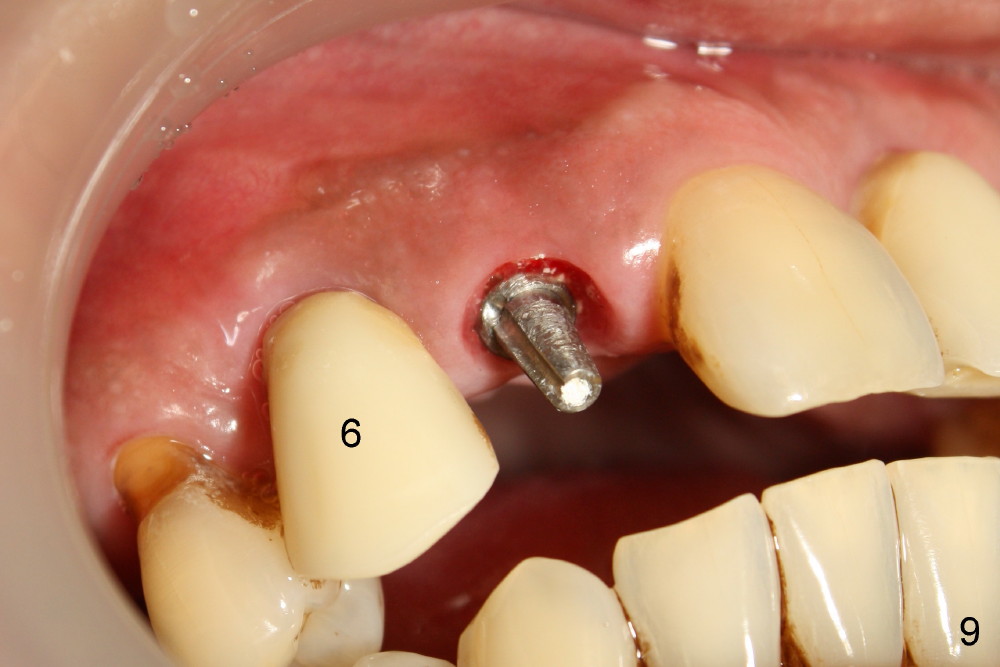

The most severely affected teeth (#6,7 and 9) are extracted and immediately replaced by 4x20 mm (#7) and 5x20 (#6,9) implants (Fig.4,5). Straight (0 degree) uniposts (3 and 4 mm, respectively) are rotated tightly into the wells of the implants by hand screw driver. In order to have reversibility to hybrid denture in the future, these uniposts are not cemented. Heavy retention grooves are placed between the uniposts and implants. Provisionals are fabricated immediately and cemented temporarily. To increase stability, flowable composite is added to the area between the provisionals of #6 and 7.

Fig.6 shows these provisionals 1 week postop. The patient is happy with the result. His diet is confined to soft food. The provisional at the site of #9 is slightly mobile.

Dear Tony and Dr. Borgner: Thanks for the input. The patient showed up today. The provisional of #7 is off (Fig.9) and then recemented and bonded to the provisional of #6 with flowable composite. Open the magnified Fig.9 to see whether the vertical groove is wide and deep enough or not. By the way, the diameters of the implant and of the abutment are 4 and 3 mm, respectively.